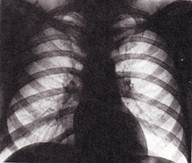

1. Определите метод лучевой диагностики и плоскость исследования.

2. На предыдущих снимках определите анатомическую область применения метода лучевой диагностики.